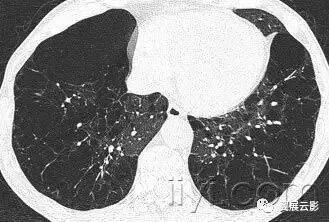

三十九、马赛克征

CT:本征象表现为不同的密度成片状镶嵌,可为间质性病变、闭塞性小气道病变(图)或者血管阻塞性疾病。马赛克征比马赛克样少血或者低灌注具有更强的诊断含义。由于支气管或细支气管阻塞导致的空气滞留可以导致局部的密度减低,在呼气相CT上表现更加明显。

该征象也可以见于间质性肺部疾病,特征是磨玻璃影,此时高密度代表间质性病变,低密度代表正常的肺。